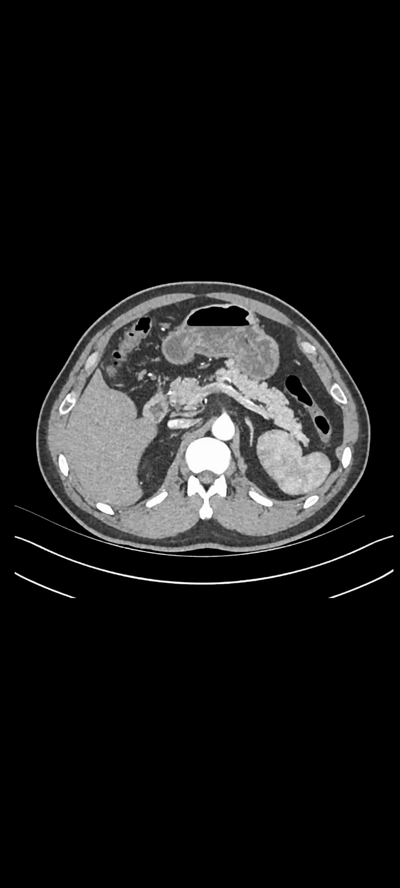

病史:患者男,59岁,发现左肾占位,增强ct